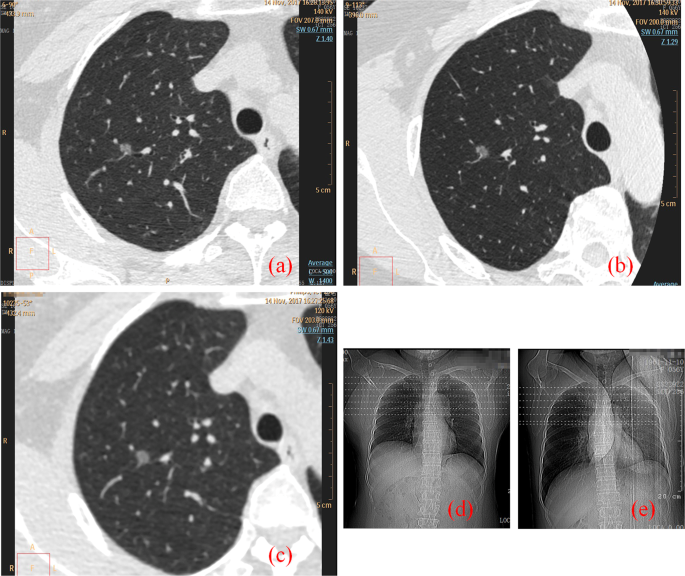

Figure 1 shows cross-sectional images of two representative cases with three CT scanning schemes. The nodule is located in the lung, and ROIs are chosen for statistical analysis. The edge of nodules and solid internal components were shown more clearly on the G-scan image than either on the B-scan image or A-scan image.

Comparison of nodule cross-sectional imaging for the three CT scanning schemes. The nodule was located in the lung. The images were provided by department of radiology of Jinhua Central Hospital to Zhejiang University and were from a 57-year-old female patient. (a,d) 1024 ultra-high-resolution scan with patients stay in supine position (B-Scan). (b,e) Breath-hold assisted ultra-high-resolution scan with patients lie in lateral position (G-Scan). (c,d) Retrospective 1024 matrix target scan with patients stay in supine position (A-Scan).

Figure 2 is comparison of local enlarged nodule images for the three CT scanning schemes. Scan scheme G improves spatial resolution and provides better detail detections of nodule structure.